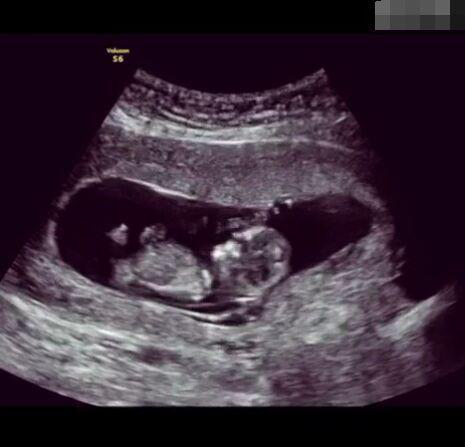

那些做了B超檢查確定胎兒男女,生下來后發(fā)現(xiàn)不對的,多半是因為在B超檢查時寶寶太調(diào)皮,以致影響了檢查準確性。就比如說,有的女寶寶在媽媽肚子里玩自己的臍帶,把臍帶夾到了兩腿中間,B超就有一定幾率拍出來好像是男寶寶的特征,導致被誤認為是男孩子。還有些男寶寶過分害羞,在做B超時雙腿緊緊并攏,醫(yī)生也很難判斷男女,只好大致猜測是女孩,就又造成了誤會。因此,B超亦不是萬能的。